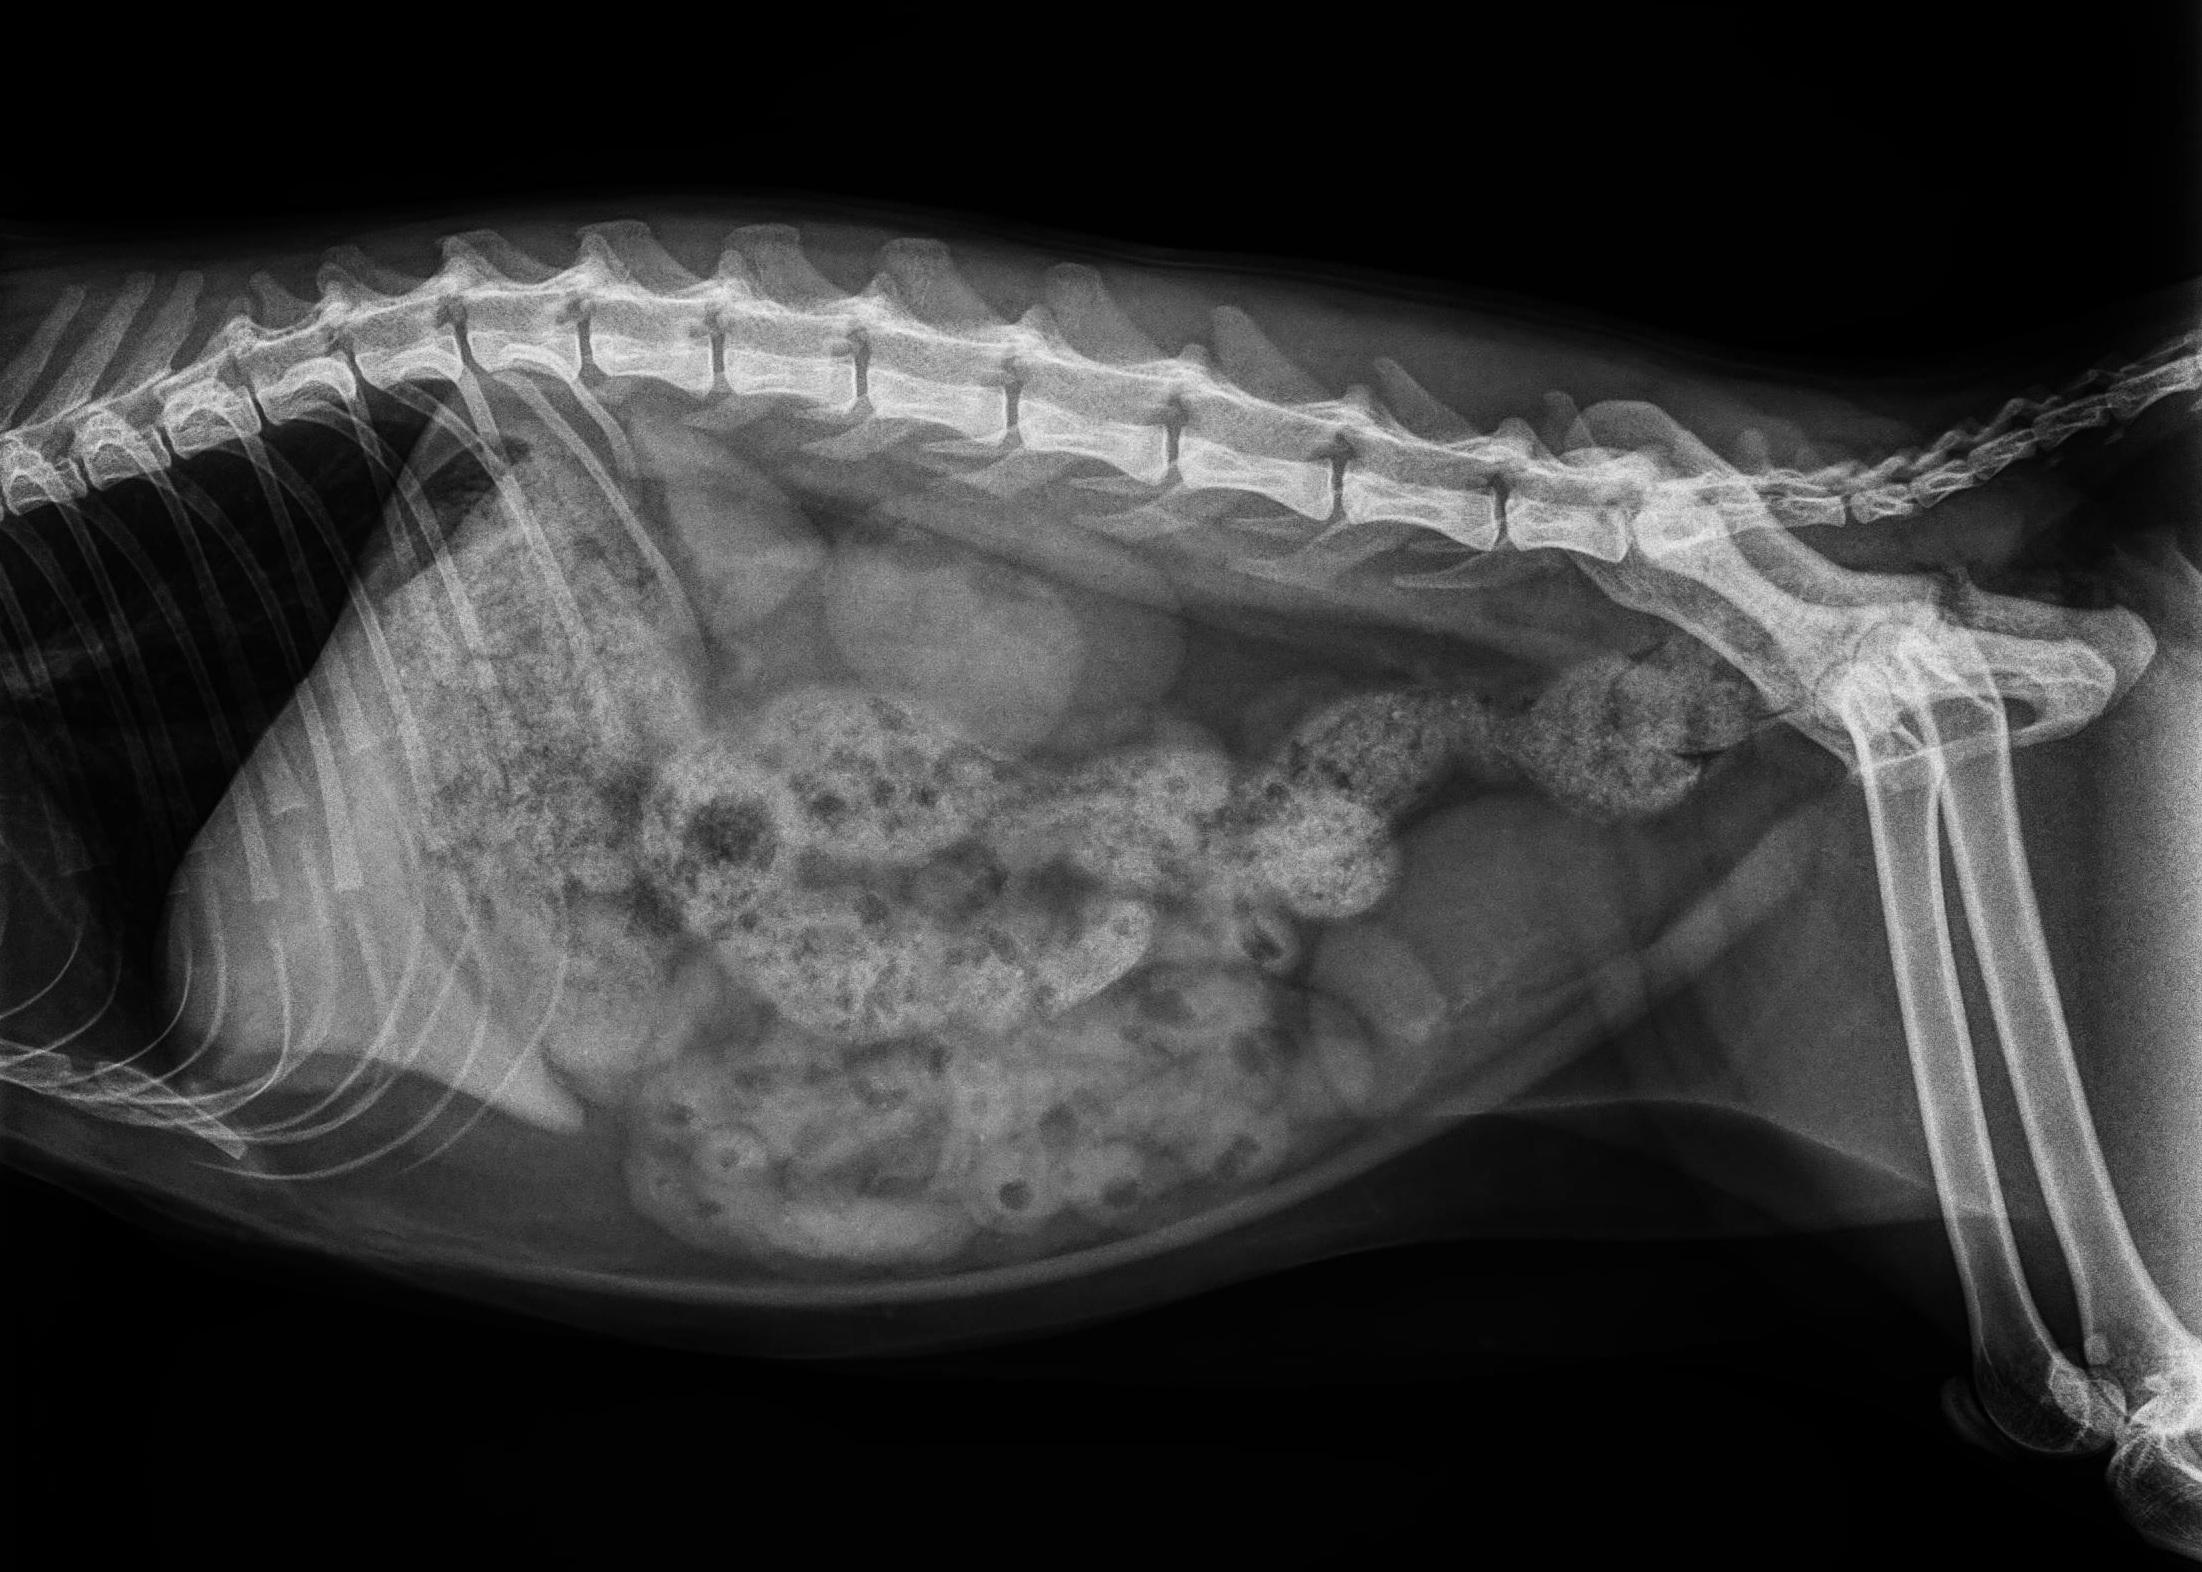

X光